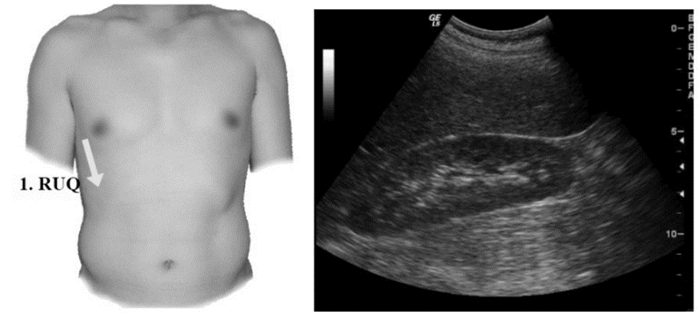

3.1.3 创伤的超声诊断的步骤及流程(1)创伤的超声诊断步骤:创伤患者床旁超声检查至少5个部位:①右上腹,也叫肝周切面、莫里森窝切面或右上1/4切面。如出现无回声区提示腹腔内出血(图 22-23)。②左上腹脾肾间隙,如出现无回声区亦提示腹腔内出血(图 24-25);③耻骨上/盆腔切面,如显示膀胱后或子宫后无回声区,提示盆腔出血可能(图 26-27);④剑突下切面,常用于探查心包有无无回声区(图 28),具体心包积液征象见2.1.2 常见异常超声心动声像图。⑤肺部超声,主要用于探查有无血气胸、肋骨骨折,具体征象见2.2肺超声。

| 图 22 肝肾隐窝部位及正常超声影像 |